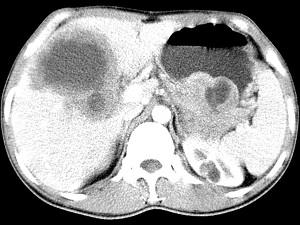

问题 女,61岁,上腹部疼痛一个月,食欲减退,消瘦,CT所见如图,最可能的诊断是 ( )

选项 A、肝包虫病 B、原发性肝癌 C、肝转移瘤 D、胃癌肝转移 E、肝脓肿

答案 D